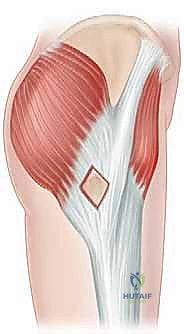

2. النوع الخارجي (External Snapping Hip)

يحدث هذا النوع على الجانب الخارجي (الوحشي) من الورك. ينجم عن انزلاق شريط من الأنسجة الضامة القوية يُسمى "الشريط الحرقفي الظنبوبي" (Iliotibial Band - ITB)، أو أحيانًا الحافة الأمامية للعضلة الألوية الكبرى (Gluteus Maximus)، فوق بروز عظمي كبير في أعلى عظم الفخذ يُسمى "المدور الكبير" (Greater Trochanter).

غالبًا ما تكون الطقطقة في هذا النوع مرئية بالعين المجردة ومسموعة بوضوح من جانب الورك. يشعر المريض وكأن مفصل الورك يخرج من مكانه ثم يعود. يترافق هذا النوع عادةً مع التهاب جراب المدور الكبير (Trochanteric Bursitis)، مما يسبب ألمًا عند النوم على الجانب المصاب أو عند صعود السلالم.